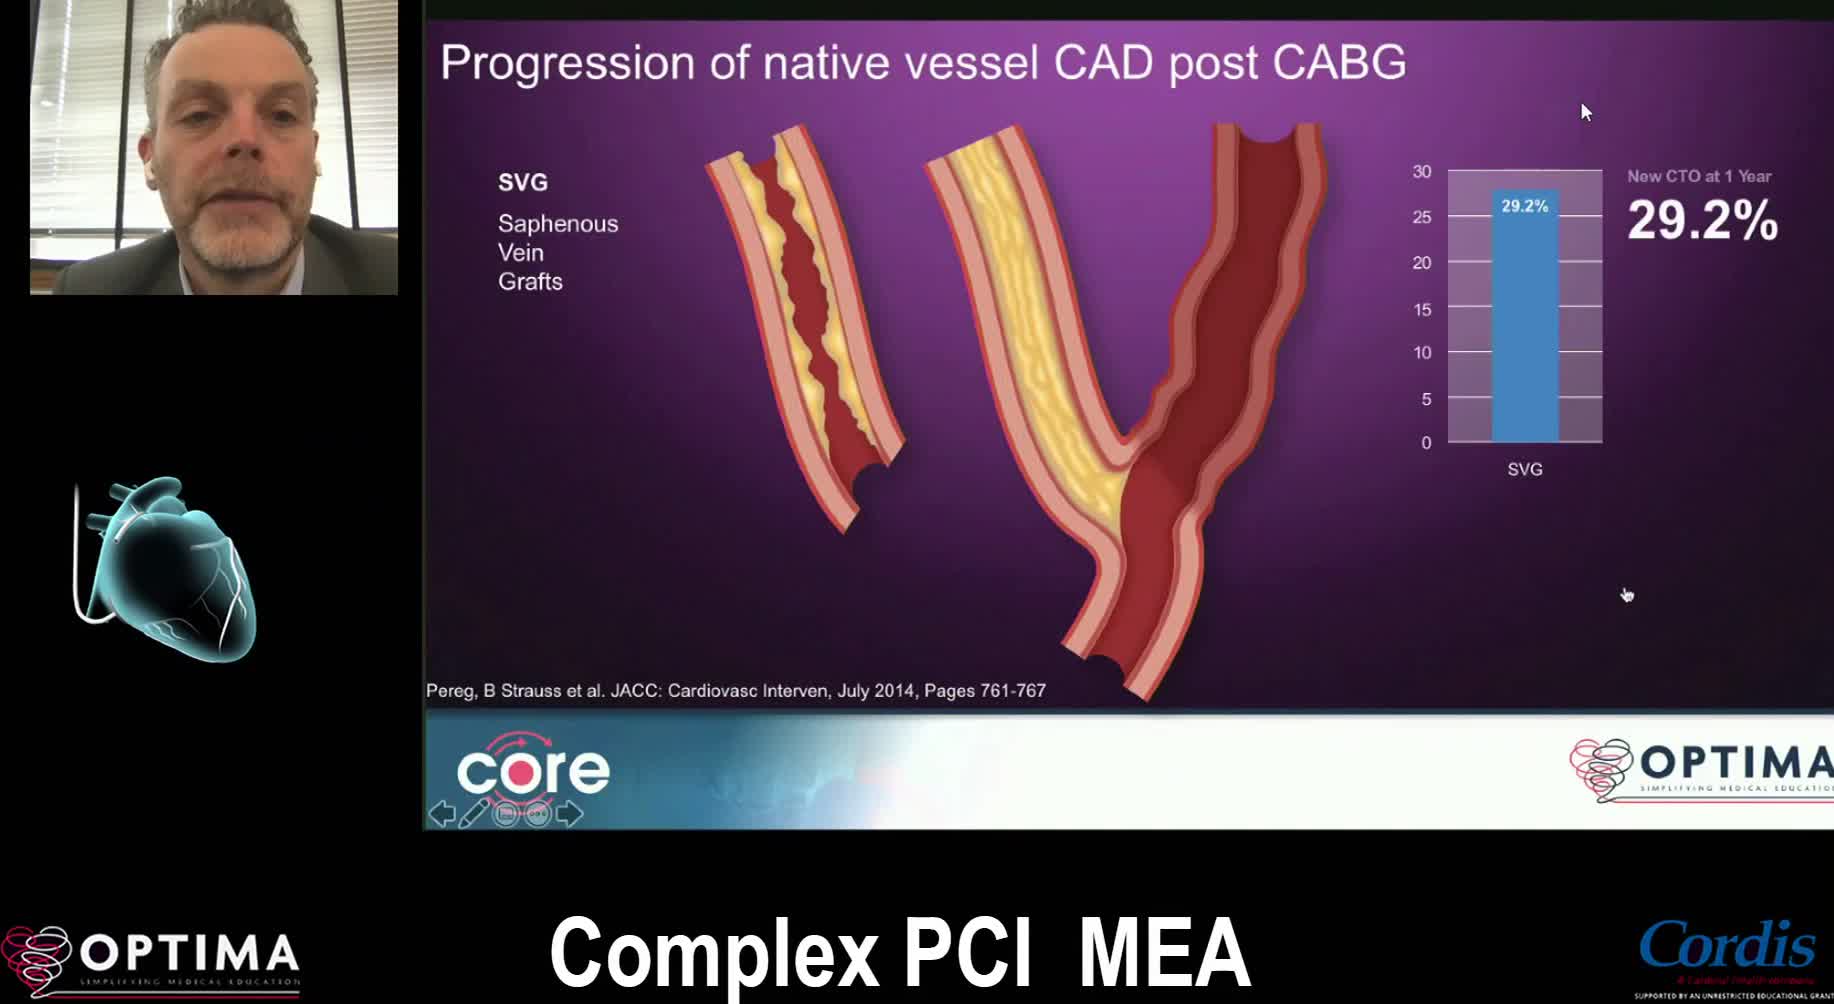

Complex PCI Middle East April 2021